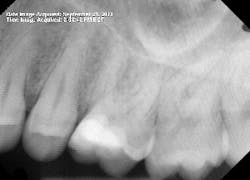

I started the root canal at 2:00 p.m. that Friday. The procedure was uneventful at first. I gained what I thought was great access, and then I started on instrumentation. Just as I began, my 0.10 TF file separated in the distobuccal (DB) canal. This was unusual since a file that large is relatively strong. It is mostly used to instrument the coronal third and rarely encounters any significant curvature.

I then successfully bypassed the file with a 15 c-file, but it separated as well. I decided there must be a hidden curve somewhere and would return to the DB canal after completing instrumentation on the remaining canals. Something interesting to note: The apex locator was not able to obtain a reading on the DB canal at any point.

By 2:22 p.m., I was taking periapical x-rays with the gutta-percha to check my working lengths and evaluate the separated files. The x-ray showed that my access wasn’t as open as I originally thought it to be. The canal curved in two places, which caused the file separations. At this point I had two separated files—the 0.1 Twisted File (TF) file and the 15 mm hand file I had used to bypass the canal.